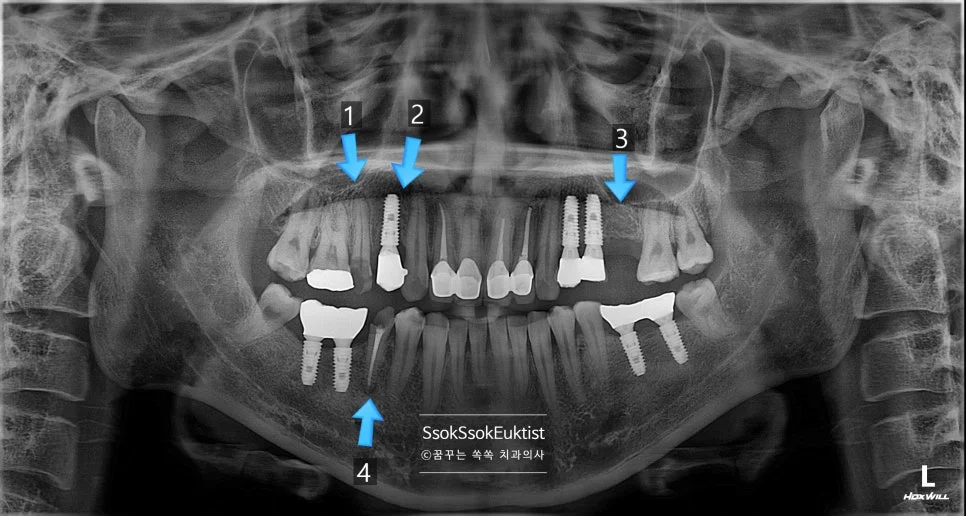

CBCT 파노라마 진단 영상 — 1~4번 치아 위치의 문제점 화살표 표시

사진에서 1번, 4번 치아의 경우 치아 머리가 너무 남지 않아 발치 후 임플란트가 필요한 상황입니다.

1번, 4번 치아의 경우 자연치아 살리기 조건 중 세 번째 조건을 만족하지 못하여 발치의 대상입니다.

한편, 3번의 경우 치아를 발치하고 오랜 시간이 지난 위치로 예쁘게 임플란트 식립을 진행하면 됩니다.

그런데 2번의 임플란트를 한번 보면 뭔가 잇몸이 부자연스러운 것을 볼 수 있는데요.

임플란트 주변에 뼈가 다 녹아내리고 그 바깥에 잇몸까지 혈류를 받지 못해 점점 괴사하고 있는 모양새입니다.

임플란트가 뼈와 유착에 성공은 하였다 하더라도 임플란트를 감싸고 있는 뼈가 부족하면 이렇게 점점 임플란트 주위염으로 뼈와 잇몸이 녹아내리게 되는데요.

이래서 임플란트는 가급적 깊게 그리고 입천장(혀) 쪽으로 위치하여 식립하여야 합니다.

이 임플란트는 점점 염증이 심해질 것이고 그나마 남아 있는 잇몸까지 녹게 되면 이후의 치료가 너무 어려워지기에 임플란트를 제거한 후 재식립을 시도합니다.